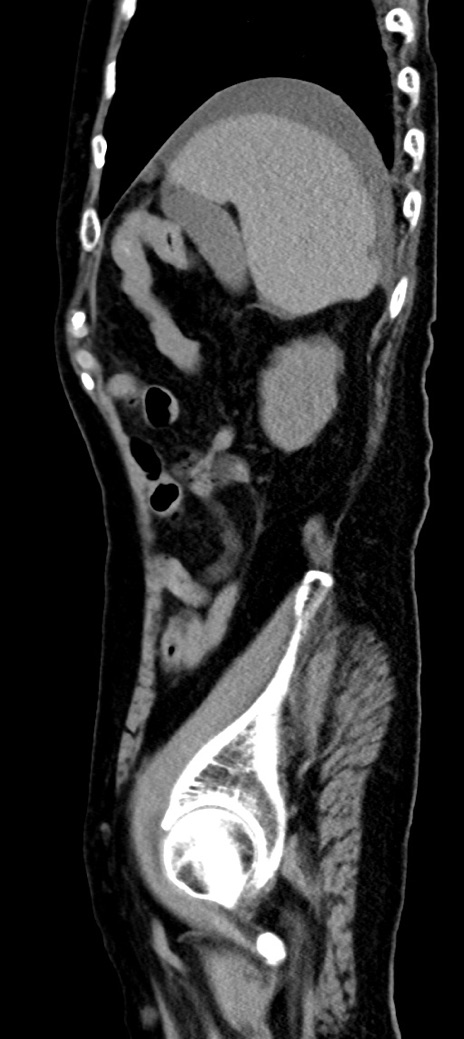

症例40(矢状断像)他院1日前

【症例】90歳代女性

【主訴】腹痛・嘔吐

【現病歴】 食欲低下、嘔吐があり昨日他院受診。肺炎と診断され入院となる。入院後より腹部全体に圧痛あり。胃管留置され経過みていたが、症状持続するため、

当院転院となる。

【既往歴】胸椎圧迫骨折、胆石症

【身体所見】腹部:中央に激痛あり、圧痛あり、反跳痛不明

【データ】WBC 17100、CRP 18.82